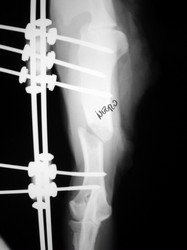

PRÁCTICAS CURSO DE FIJACIÓN EXTERNA PERFECCIONAMIENTO.

Húmero.